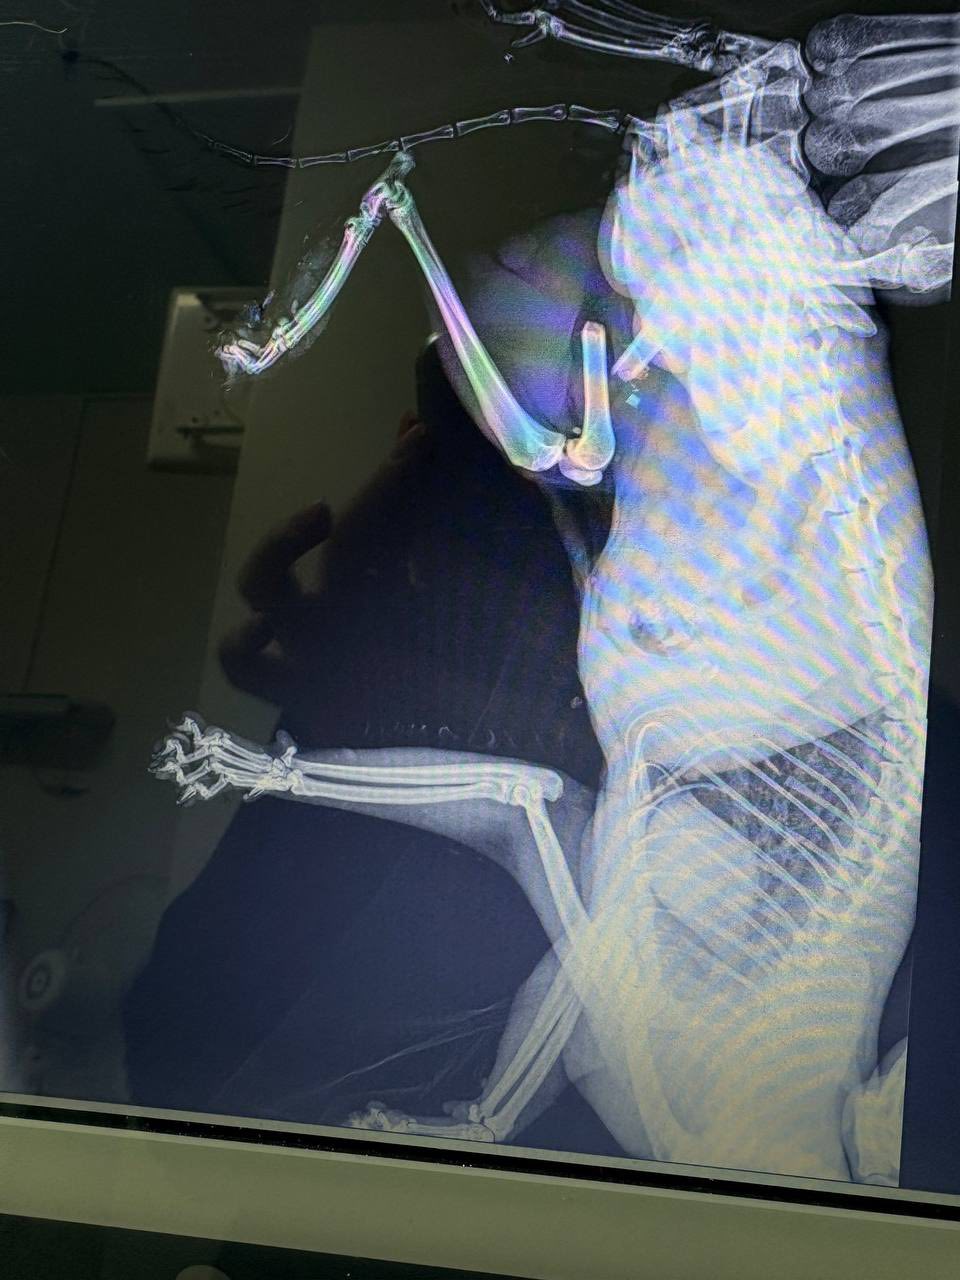

По данным КП, кота по имени Сережка привезли военные. Его состояние было тяжелым: открытый перелом правого бедра, рваные раны на тазовых конечностях.

Врачи Центра провели сложную операцию – остеосинтез правого бедра, а также назначили интенсивную терапию.